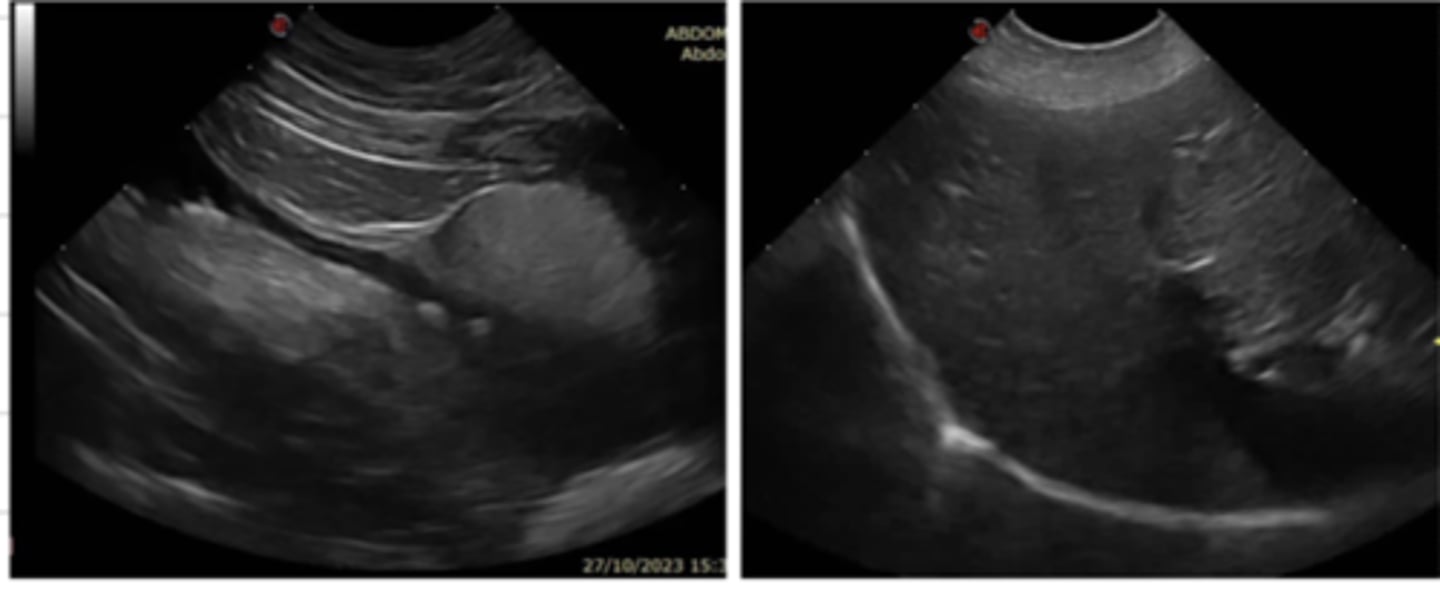

ultrasonography

what imaging technique is being used?

ultrasonography

these images were produced with what type of imaging?

ultrasonography

this terminology is used for what type of imaging technique?

ultrasonography

radiography is complementary with what other imaging technique? (frequently performed together)

radiography

ultrasounds are frequently performed with what other imaging technique?

-abdominal ultrasounds

-pregnancy diagnosis

-echocardiography

-noncardiac chest ultrasounds

-ocular ultrasounds

-superficial tissues (neck, mammary glands, subcutaneous tissue)

-musculoskeletal ultrasounds

-fine needle aspirations/biopsies

what are the frequent uses of ultrasonography?

ultrasonography

what imaging technique is commonly used for pregnancy diagnosis?

ultrasonography

what imaging technique is commonly used to guide the vet for a fine needle aspiration or biopsy?